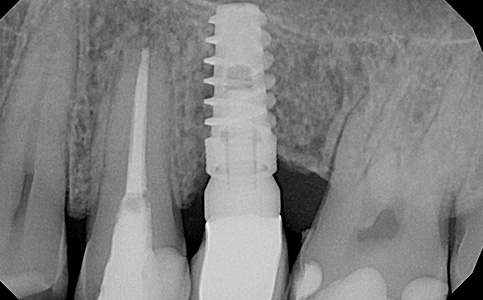

Przykład uzupełnienia pojedynczego braku zęba implantem. Implant imituje korzeń zęba, który w połączeniu z koroną protetyczną tworzy pełnowartościowy ząb.